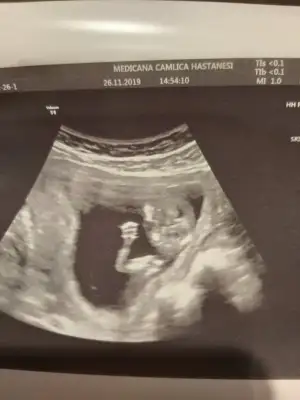

Kaçıncı hafta canım , çok tatlış ya:) maşallahKizlar bebis fotosuyla geldim

Eki Görüntüle 2559113

Doktoru soranlar olmuştu medicana dr.hüseyin arık herşeyi sordum gönül rahatlığıyla güler yüzle gayet iyi bir dr devam edicem doktorumu buldum çok şükür tavsiye ederim dr çok önemli sizi dinliyor motive ediyor.

Teyzelerine el salladı size![]()